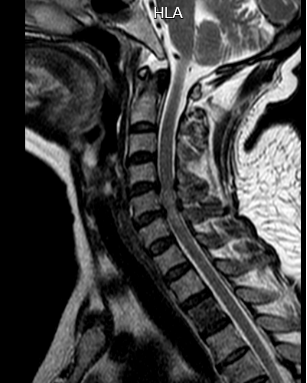

术前

我院副院长、骨科主任张勇华与省人医脊柱外科帮扶专家陈崇博士研究讨论认为:患者有颈椎发育性椎管狭窄及颈椎间盘突出的基础病变,外伤后出现“挥鞭样损伤”,入院时表现为“四肢不全瘫”症状,从MR看其颈4-6节段脊髓变性。为了挽救脊髓功能,须尽快手术解除颈脊髓的压迫,以利于病情恢复。虽然因为转诊、路途等因素,救治时间已经过去近48小时,已不在脊髓救援的“黄金时间”,但患者及家属仍然坚信,佛冈县人民医院仍然是人民性命相托的人民医院,是疾病救援的“生命绳索”。